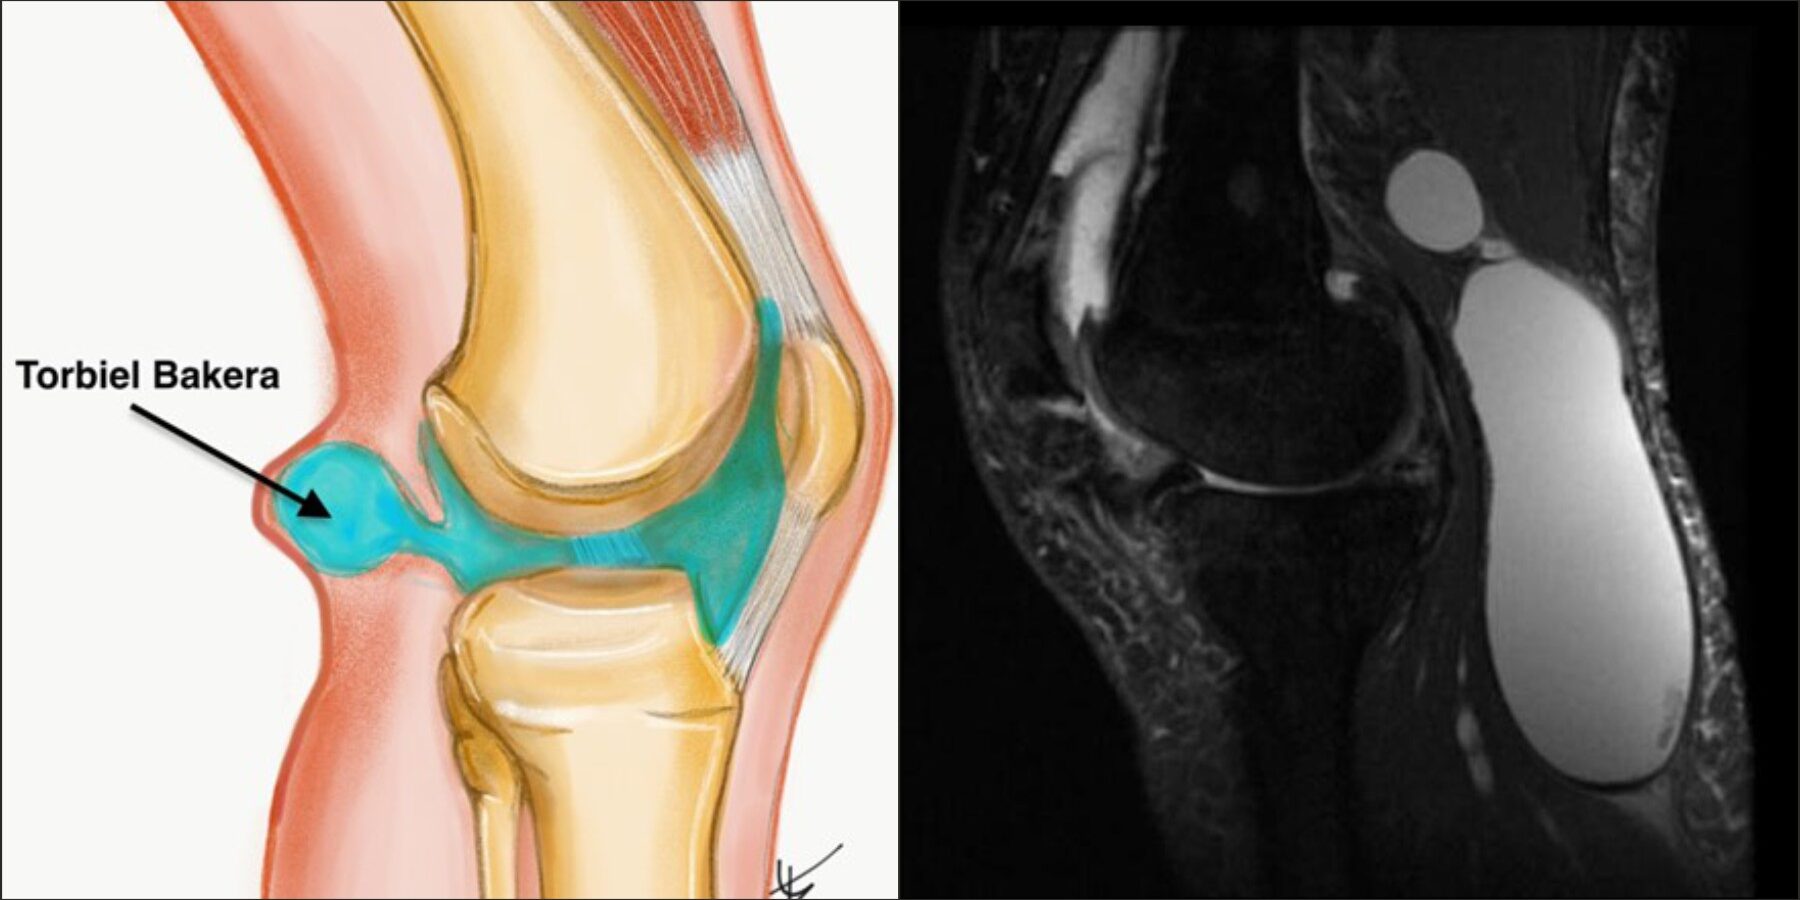

Torbiel Bakera, czyli torbiel podkolanowa, to wypełniona płynem masa, będąca rozdęciem kaletki maziowej w dole podkolanowym, najczęściej kaletki brzuchato-łydkowo-półbłoniastej. Ta kaletka jest wyjątkowa, ponieważ w przeciwieństwie do innych kaletek okołostawowych, komunikuje się ze stawem kolanowym poprzez otwór w torebce stawowej, za kłykciem przyśrodkowym kości udowej. Kaletki maziowe to wypustki błony maziowej. Ich zadaniem jest ochrona, zmniejszenie tarcia i ucisku oraz ułatwienie poślizgu w miejscach wrażliwych. Torbiel formuje się typowo pomiędzy ścięgnem mięśnia półbłoniastego (m. semimembranosus), a przyśrodkową głową mięśnia brzuchatego łydki (m. gastrocnemius)1. Torbiele podkolanowe rzadko występują samodzielnie i najczęściej występują w połączeniu z innymi patologiami wewnątrzstawowymi i stanami zapalnymi, takimi jak choroba zwyrodnieniowa stawów, uszkodzenia łąkotki i reumatoidalne zapalenie stawów. Uszkodzenia wewnętrza stawu prowokują błonę maziową do nadmiernej produkcji płynu stawowego, który ewakuuje się do cysty. U dzieci natomiast cysty mogą występować pierwotnie jako wynik przepukliny tylnej torebki stawowej.

Rezonans magnetyczny cysty Bakera (MRI)

Rezonans magnetyczny nie tylko potwierdza obecność cysty, ale umożliwia dokładną ocenę współistniejących patologii wewnątrzstawowych10. W obrazach T2-zależnych cysta prezentuje się jako jednorodny obszar wysokiego sygnału położony w dole podkolanowym z charakterystycznym połączeniem ze stawem11. MRI jest szczególnie przydatne w planowaniu leczenia operacyjnego oraz w diagnostyce różnicowej, umożliwiając odróżnienie cysty od torbieli łąkotki, guzów, tętniaków czy krwiaków. Zdjęcia 1,2